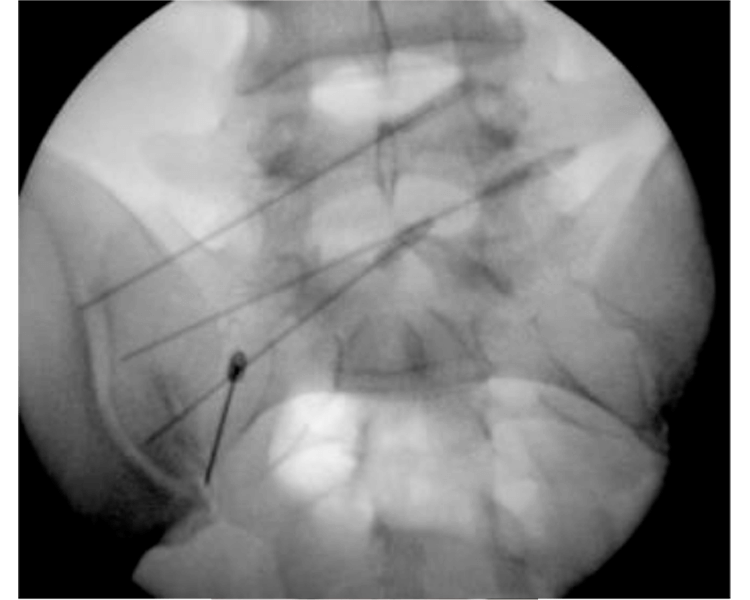

O Procedimento: Precisão Guiada por Imagem

O grande diferencial da infiltração na coluna é a precisão. O procedimento é sempre guiado por métodos de imagem. Os mais comuns são a fluoroscopia (um tipo de raio-X em tempo real), a tomografia computadorizada e o ultrassom.

Essa tecnologia permite que o médico visualize a coluna vertebral em detalhes. Assim, a agulha pode ser inserida com extrema exatidão no local desejado. Isso garante que o medicamento seja entregue diretamente na fonte da dor, maximizando a eficácia.

Durante o procedimento, um contraste pode ser injetado. Isso ajuda a confirmar a posição correta da agulha e a distribuição do medicamento. O médico acompanha todo o processo em um monitor, assegurando a segurança e a precisão